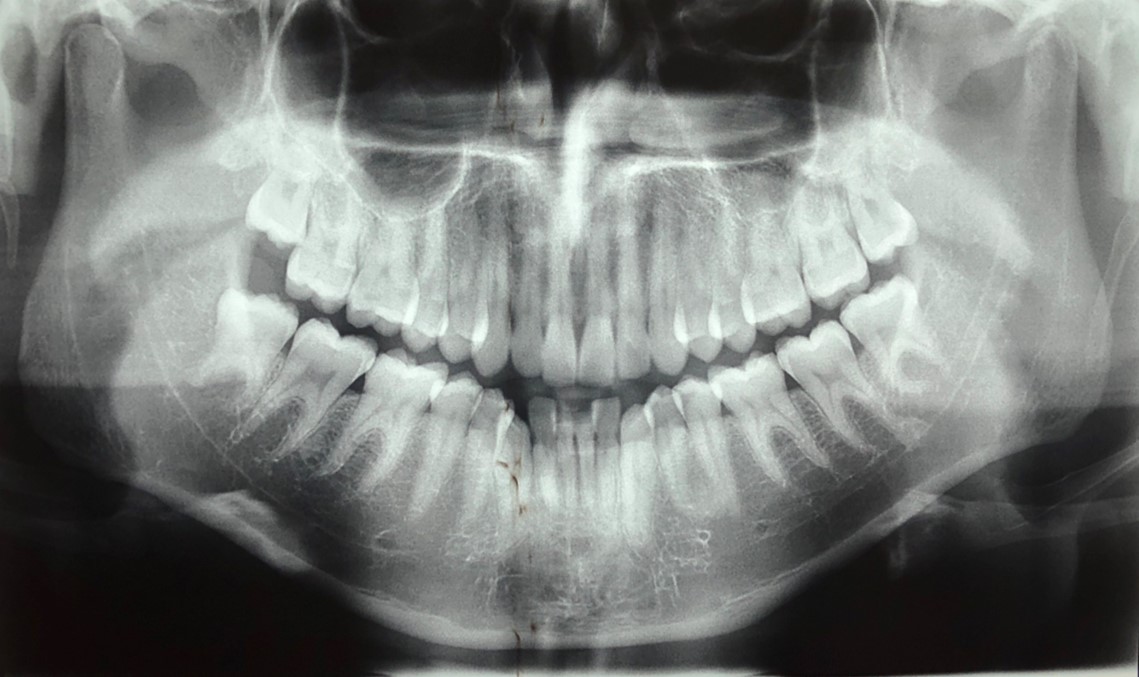

O cisto odontogênico calcificante (COC) foi primeiramente descrito em 1962, considerado como condição patológica benigna de ocorrência rara em maxila e mandíbula, caracterizado por revestimento cístico de células epiteliais odontogênicas contendo células fantasmas com propensão a regiões de calcificação. Neste artigo, descreveu-se a configuração clínica e histopatológica do COC por meio de relato de caso submetido a tratamento cirúrgico e acompanhamento pós-operatório. Uma paciente de 11 anos apresentou um aumento de volume em região maxilar a esquerda próxima ao sulco nasolabial sem sintomatologia dolorosa. Os exames radiográficos indicaram lesão radiolúcida, bem circunscrita e expansiva em maxila, que foi submetida a enucleação associada a ostectomia marginal das paredes corticais ósseas. O quadro histopatológico foi caracterizado por revestimento cístico com epitélio odontogênico ameloblástico, ninhos espalhados de células fantasmas e regiões eosinofílicas de material compatível com dentinóide. O relato de caso apresentou perfil clínico de COC, que pode ser confundido com outras lesões císticas ou tumorais, sendo essencial diagnóstico por meio de análise histopatológica. A abordagem cirúrgica proporcionou diagnóstico e tratamento. Após acompanhamento clínico e radiográfico, não houve recorrência do COC.